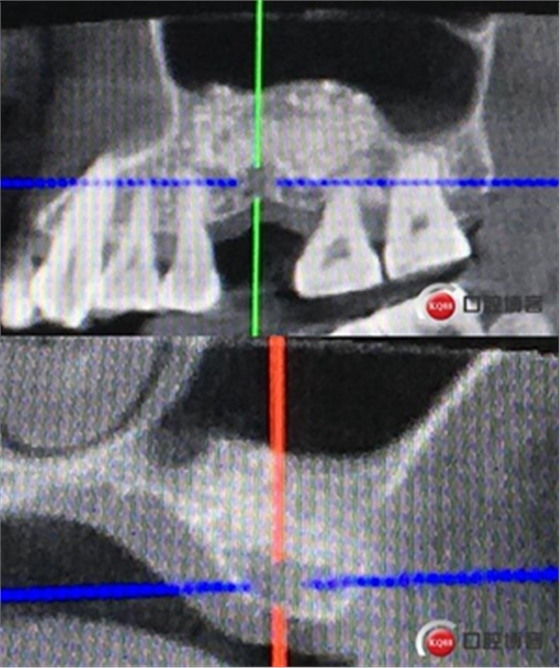

骨高度僅有3mm,寬度充足。計劃外提升,根據(jù)骨質(zhì)情況決定是否同期植入植體,切開翻瓣,暴露上頜竇頰側(cè)骨壁。

骨高度比曲斷片顯示的更低,不利于同期植入,直接縫合。

術(shù)后X光片,植骨量充足。

術(shù)后8個月,X光顯示骨量充足,密度明顯增加。